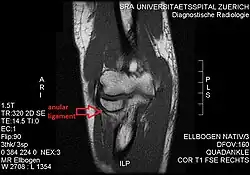

The supinator muscle -

T1 weighted MRI showing the anular ligament -